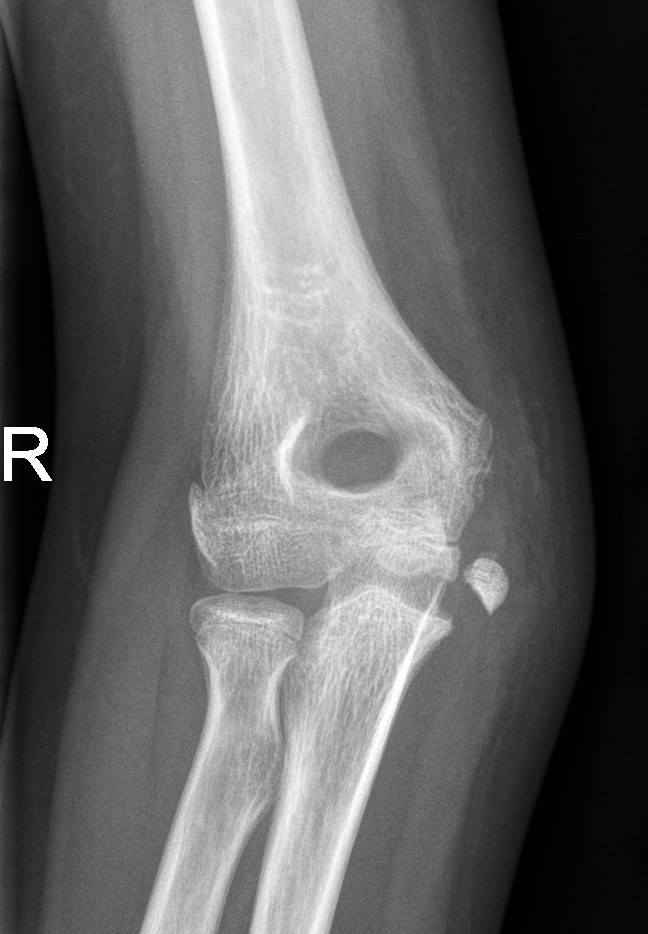

Medial Epicondyle Fractures

- Medial epicondyle fractures are often missed because they are mistaken as an ossification centre. Assess ulnar nerve function in any medial epicondyle fracture.

- Discuss with the Orthopaedic team for further management.

Displaced medial epicondyle